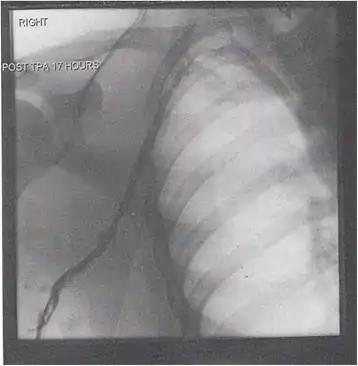

Thrombolysis is the injection of an enzyme into the veins to dissolve blood clots, and while this treatment has been proven effective against the life-threatening emergency clots of stroke and heart attacks, randomized controlled trials[139][140][141] have not established a net benefit in those with acute proximal DVT.[5][142] Drawbacks of catheter-directed thrombolysis (the preferred method of administering the clot-busting enzyme[5]) include a risk of bleeding, complexity,[lower-alpha 12] and the cost of the procedure.[125] Although, while anticoagulation is the preferred treatment for DVT,[125] thrombolysis is a treatment option for those with the severe DVT form of phlegmasia cerula dorens (bottom left image) and in some younger patients with DVT affecting the iliac and common femoral veins.[12] Of note, a variety of contraindications to thrombolysis exist.[125] In 2020, NICE kept their 2012 recommendations that catheter-directed thrombolysis should be considered in those with iliofemoral DVT who have "symptoms lasting less than 14 days, good functional status, a life expectancy of 1 year or more, and a low risk of bleeding."[138]

A venogram before catheter-directed thrombolysis for Paget–Schroetter syndrome, a rare and severe arm DVT shown here in a judo practitioner, with highly restricted blood flow shown in the vein

After treatment with catheter-directed thrombolysis, blood flow in the axillary and subclavian vein were significantly improved. Afterwards, a first rib resection allowed decompression. This reduces the risk of recurrent DVT and other sequelae from thoracic outlet compression.[147]